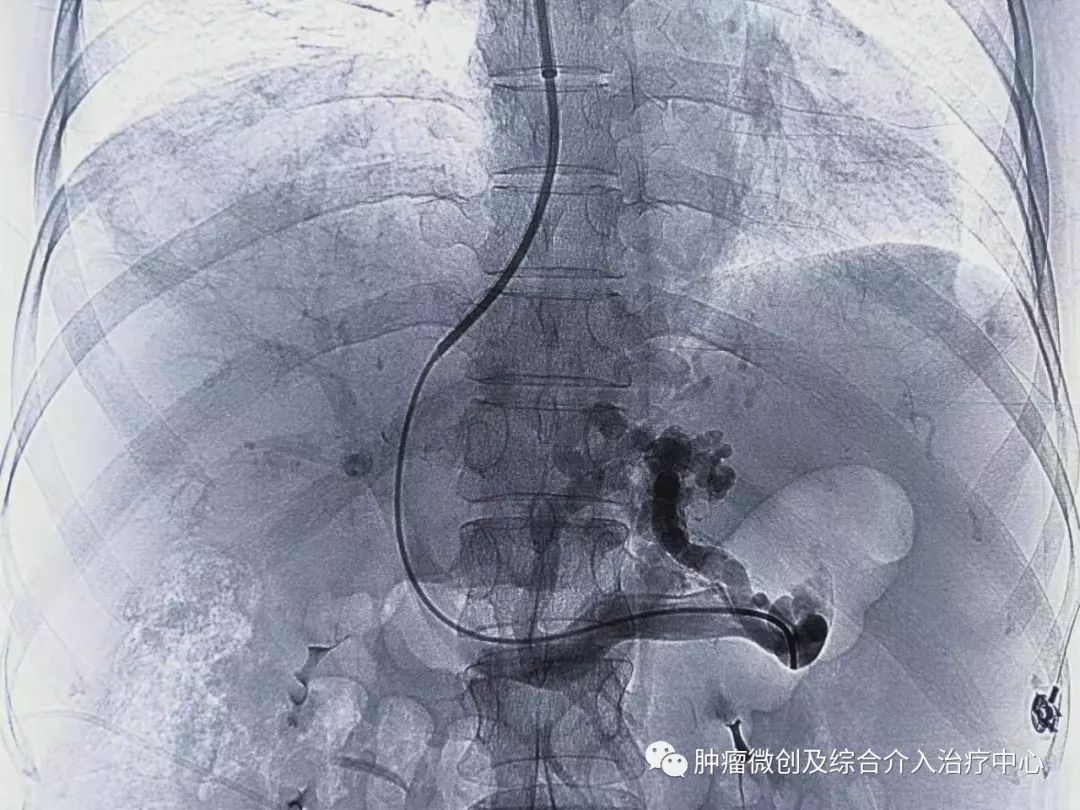

经过静脉穿刺进入门脉系统:

栓塞消化道出血责任血管:

再次造影可见:门脉血流流向-体静脉达到分流目的,术前侧压力42,术后25,门脉压力明显降低,达到防止再次出血目的。